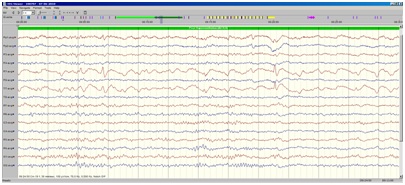

De små strømme kan give synlige udslag, og vises på en skærm. Tidligeret skrev man med penne på en kørende papirstrimmel, i dag er processen digital og stregerne vises på en skærm (fig. 1).

Fig. 1 Normalt EEG

Normalt EEG fra en voksen person.

Midt i kurven (markeret gråt øverst i kurven)åbner patienten øjnene, og man ser her, især i de to nederste kanaler, at kurvebilledet ændrer sig fuldstændigt, kurven ”flader ud”, og den regelmæssige aktivitet (den såkaldte alfa-rytme) forsvinder; dette er en normal reaktion, når man åbner øjnene, eller foretager sig noget mentalt, f eks hovedregning).

EEG signalerne afhænger af, om man er vågen eller sover, og de ændrer sig på karakteristisk måde med alderen; fra nyfødte til yngre voksne ændrer kurvebilledet sig meget kraftigt, mens der fra cirka 20 års alderen kun sker beskedne ændringer